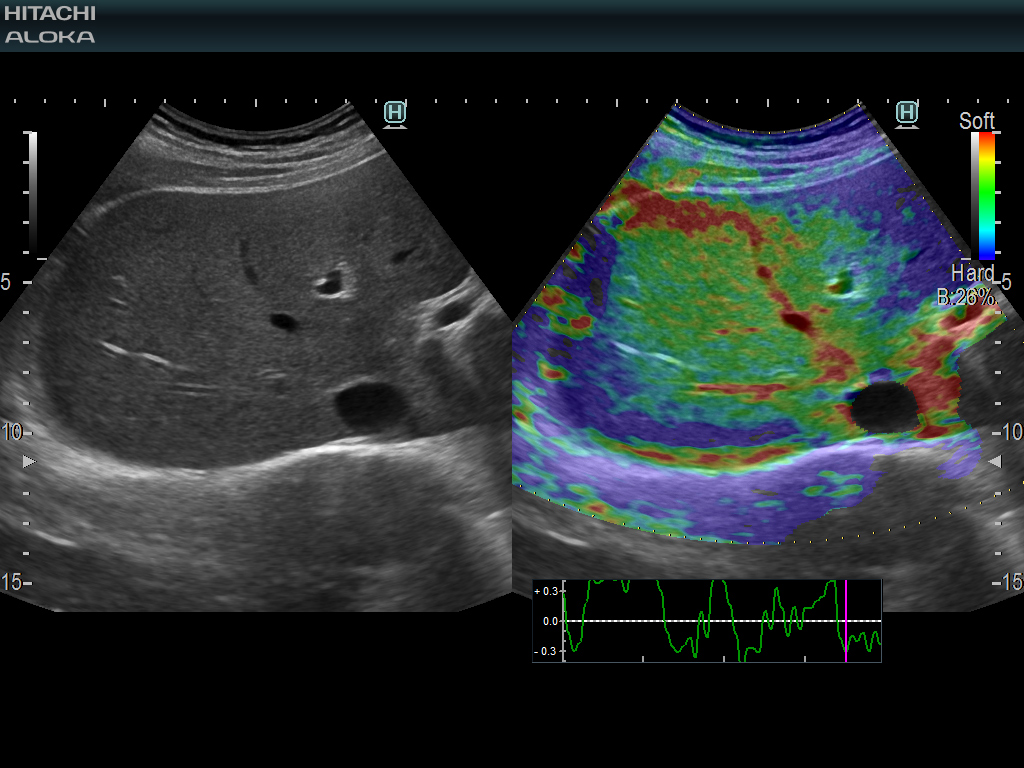

193/5000 RTE는 실시간으로 조직 변형을 평가하고 조직 강성의 측정 된 차이를 컬러 맵으로 표시하여 예를 들어 C 형 간염 환자의 섬유증 병기 결정을 추정합니다.

145/5000 조직의 평가를 허용하고 전단파 속도 측정의 객관적인 평가를위한 추가 신뢰성 지표를 제공합니다.